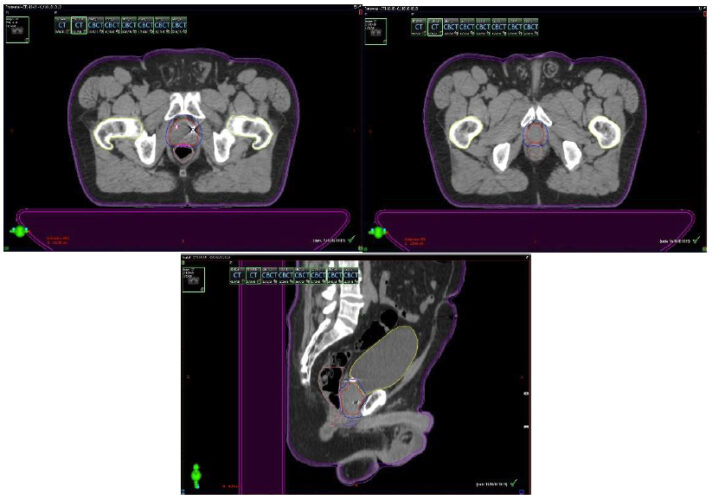

Se presentan figuras de un caso clínico de nuestro centro. Paciente de 57 años, APE: 6.5, Biopsia Gleason 7 (3+4) 2/6 sextantes. Etapificación (-), Rechaza cirugía.